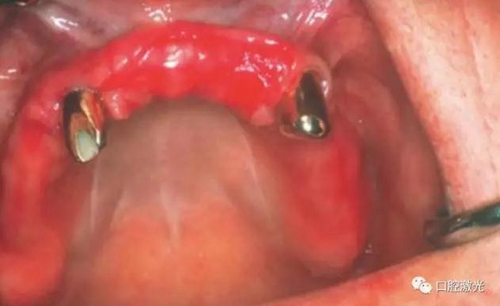

對(duì)患者實(shí)施局部麻醉,隨后在種植體位置進(jìn)行翻瓣。利用塑料刮治器將肉芽組織清除干凈,并將翻瓣邊緣削薄。此時(shí)在種植體周圍可見明顯骨缺失。

利用半導(dǎo)體激光照射已經(jīng)暴露的種植體表面。激光輸出功率1.0W,連續(xù)模式,照射時(shí)間20秒,光纖芯徑400um,光纖尖不初始化。由于激光的選擇性吸收的特點(diǎn),該激光能量設(shè)定足以殺滅導(dǎo)致種植體周圍炎的厭氧菌,卻不會(huì)對(duì)種植體表面和種植體周圍生物組織(骨組織、黏膜組織)造成熱或者機(jī)械損害。在軟組織恢復(fù)6周和12周后分別再進(jìn)行一次激光滅菌治療(參照牙周炎激光滅菌程序)。